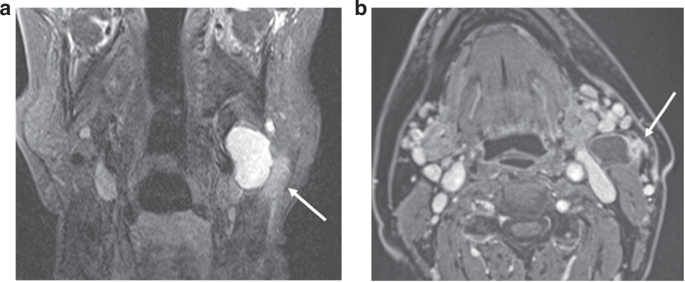

iENE assessment is highly dependent on good quality imaging and we found significant heterogeneity in image quality (especially MRI) in the PATHOS cohort, with 18.6% of images acquired over the 9-year recruitment period being deemed suboptimal. The two centres where staging scans were performed in a small number of centralised, high-volume sites had a significantly lower rate of suboptimal imaging than the third centre where imaging was performed across a larger number of referral sites. Factors affecting image quality include post-contrast slice thickness and multiplanar image analysis. These differences are rarely due to different MRI or CT protocols but rather a combination of factors including system quality, radiographic technique and radiologist supervision. Major pENE, defined as >2 mm ENE, may not be reliably detected with imaging slice thickness ≥3 mm due to partial volume artefact (averaging of signal from adjacent small structures into single voxel), and minor pENE ( ≤ 2 mm) will be missed altogether. Furthermore, as lymph nodes in the deep cervical chain are aligned longitudinally along the jugular vein, nodal coalescence will tend to occur along this axis, thus multiplanar assessment of both coronal and sagittal images is needed to accurately identify nodal coalescence (iENE grade 2). Iatrogenic changes are another confounder and 38% of study cases (111 patients) underwent a core nodal biopsy prior to their staging CT and/or MRI scans. Knowing if and when a core biopsy has been carried out is imperative before cross-sectional imaging is reviewed for iENE, as iatrogenic biopsy effects can vary from minimal perinodal fat-stranding to changes that mimic grade 3 iENE, examples of which are shown in Figs. 4 and 5. Following the 1st round of radiology reviews, it was agreed that any potential biopsy-related changes should be discounted and not recorded as iENE for the 2nd (final) round reviews, following general TNM principles (14). This obviously has a potential for producing false negative results where genuine iENE features are masked by iatrogenic change and we saw the highest proportion of recent (<30 day) core biopsies in the iENE-/pENE+ group. Conversely core biopsy may also produce false positives if biopsy related findings are interpreted as positive iENE features, particularly if the reporting radiologist is unaware of recent biopsy (Figs. 4 and 5).